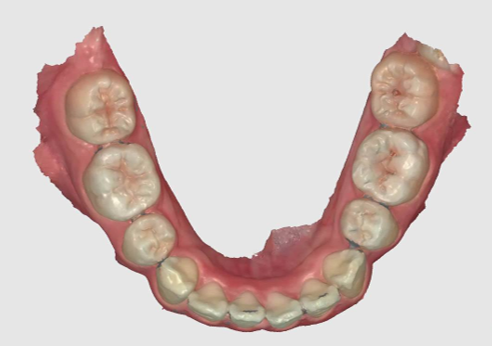

Intra Oral Scanning

This can replace tradition impression taking with trays and impression materials. Allowing a digital 3D record of the dentition to be used for educating patients, monitoring the dentition or used for making prostheses. The efficiency of making prostheses is improved with images being sent straight to the laboratory and not relying on couriers to transport impressions to the laboratory.